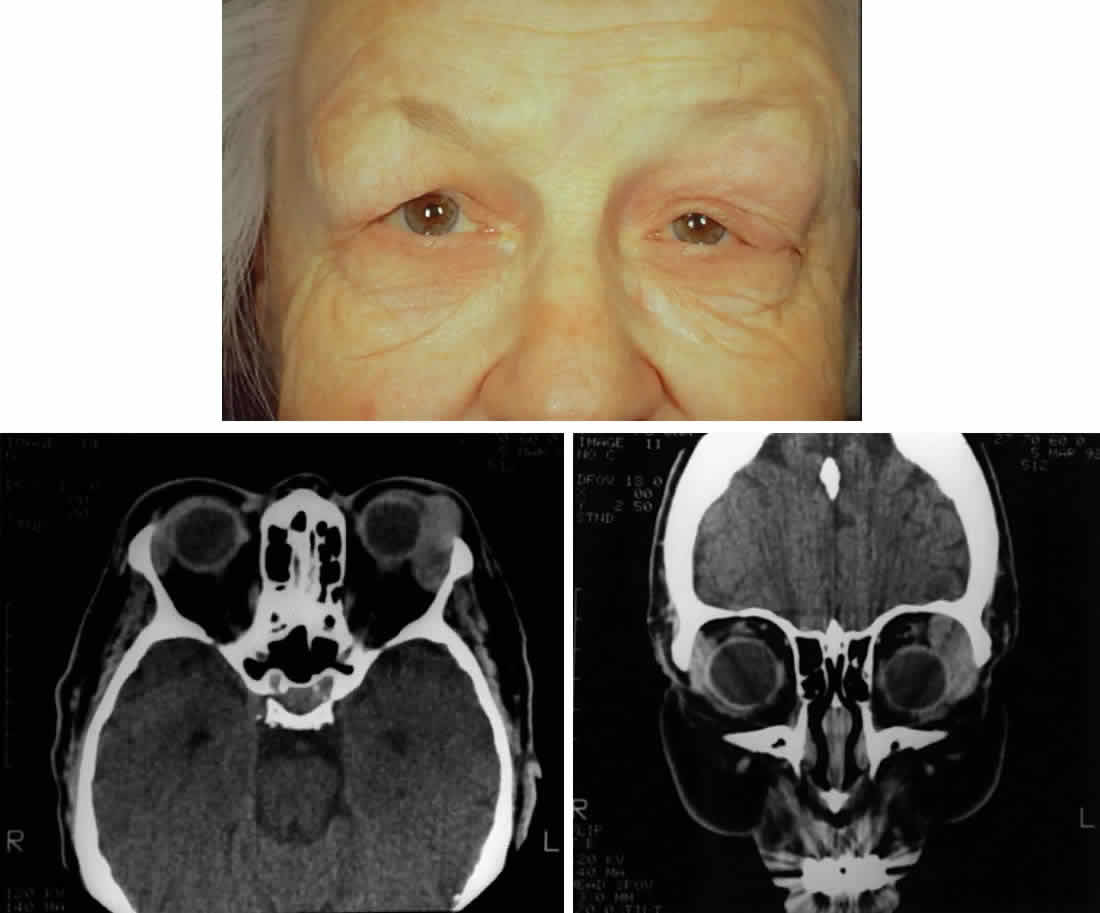

Fig. 2. A 68-year-old woman with malignant lymphoma. A. Clinical photograph demonstrating fullness over the left lacrimal gland fossa, S-shaped contour of the upper eyelid, asymmetric superior sulci, and ptosis. Inflammatory signs are absent. B. Axial computed tomograph demonstrating the classic well-demarcated, oblong appearance of lymphoproliferative diseases of the lacrimal gland. Note that the lesion extends beyond the anterior orbital rim. C. Coronal computed tomograph of the same lesion. Note that the lesion contours to the globe and bone and does not produce any bone changes.

In patients with lymphoproliferative infiltration of the lacrimal gland, a firm, rubbery mass is often palpable in the lacrimal gland fossa. In contrast to inflammatory lesions, lymphoid lesions are usually not tender. Lymphoid lesions contour to the shape of the fossa and surrounding structures, producing a well-demarcated, oblong mass on computed tomography (see Figs. 2B and 2C).9,31 Prominent enhancement after intravenous administration of contrast material is typical for lymphoid lesions.31 The amount of enhancement is similar to enhancement of extraocular muscles. Anterior extension beyond the orbital rim indicates palpebral lobe involvement, which is more typical of lymphomatous lesions and very rare for epithelial tumors of the lacrimal gland.30 In addition, destruction of bone is rare with lymphomatous lesions and therefore is useful in distinguishing lymphomatous lesions from malignant epithelial tumors.9